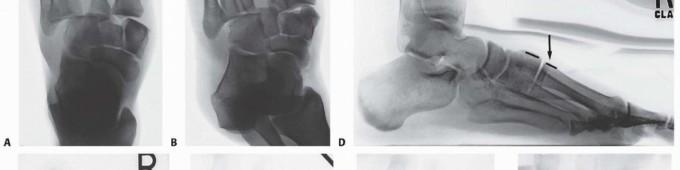

Computed tomography (CT) scanning may also be beneficial in the instance of a subtle Lisfranc injury, particularly in a polytrauma patient or a patient with multiple extremity injuries that preclude weight-bearing radiographs, and in delineating proximal fracture line extension into the navicular, cuboid, or cuneiforms (

FIG 4

).

• CT scan showing displacement through second tarsometatarsal and intercuneiform articulations (

A

) and intra-articular fractures of navicular and cuboid (

B

,

black arrows

) in a different patient.